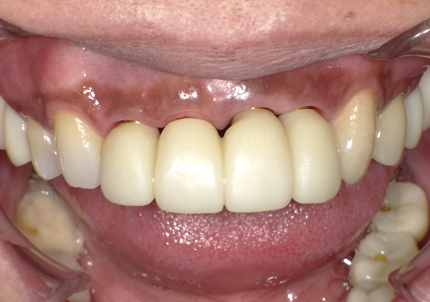

22.最終補綴物完成・装着口腔内写真(2021年1月)

24.口腔内写真

【 2018年 術前 】

【 2025年5月 現在 】